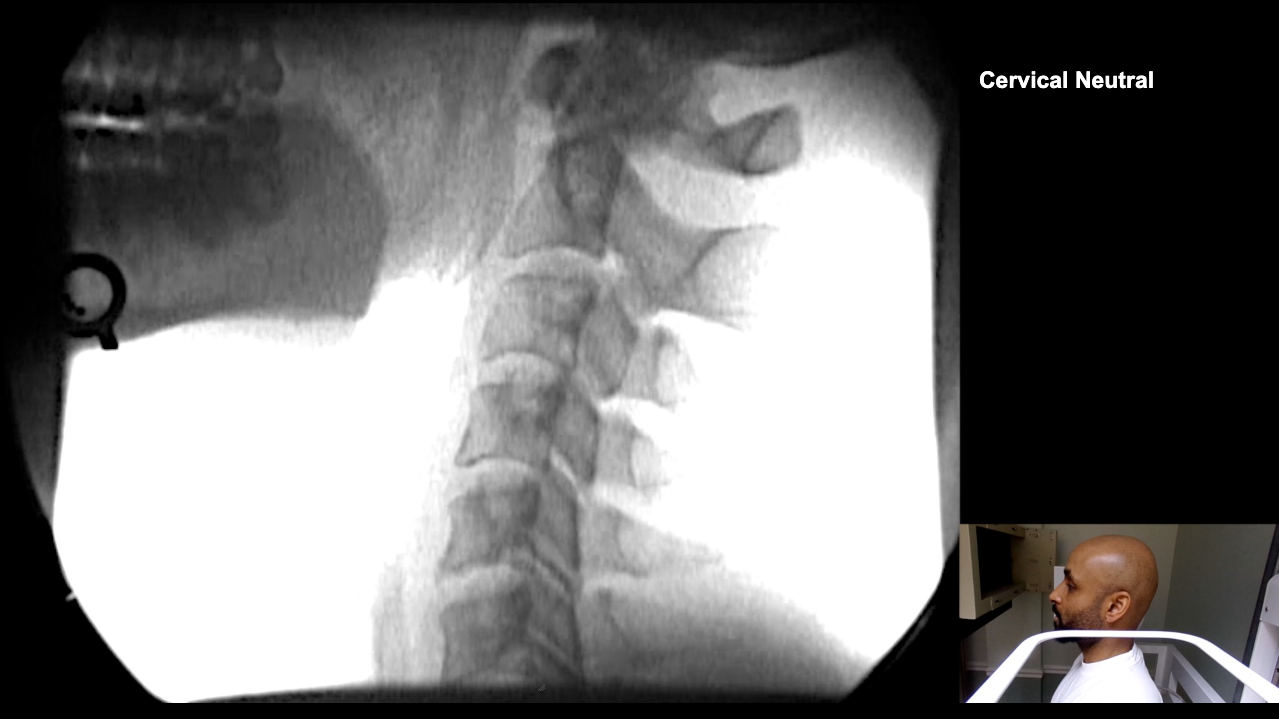

Image 2